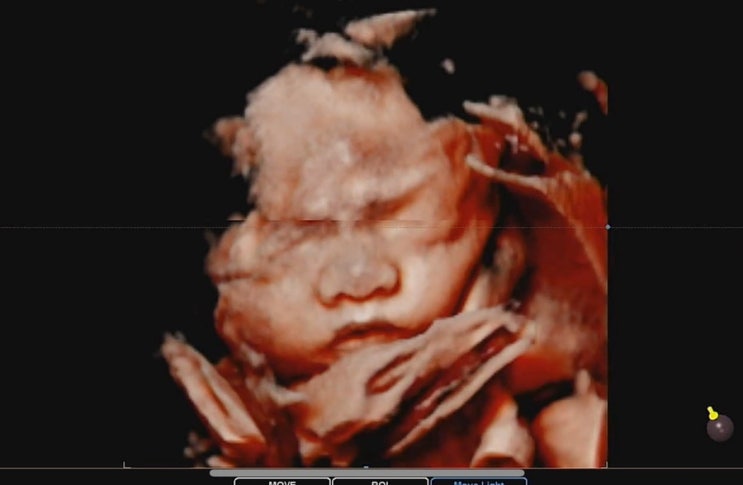

임신 27주차 일상 / 임당 산모 식단 관리, 태교 여행 출발

지난 주 임당을 확정 받고 식단 시작 재검때 3,4차 검사 혈당만 좀 튀어서 단 거 안 먹고 식후 운동하라고 ...